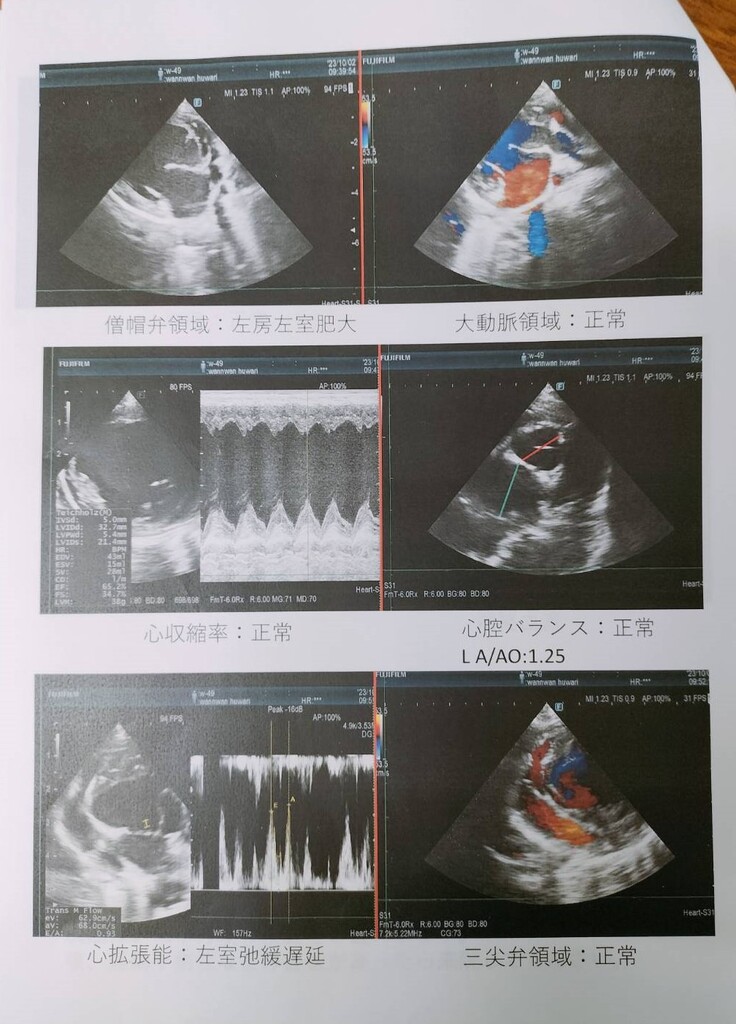

Y動物病院にて診療すると、動脈管開存症(PDA)であることがわかり、手術のできるR動物病院を紹介していただきました。

すぐ、Y動物病院で診てもらったところ、動脈管開存症(PDA)と診断され、手術のできるR動物病院を紹介していただきました。

メスの4歳チワワです。心臓の動脈管開存症(PDA)と診断され、一刻も早く手術をしたほうが良いと先生からのお話しをいただきまして、緊急で手術をしました。

チワワのふわりちゃんは心臓の動脈管開存症との診断でした。